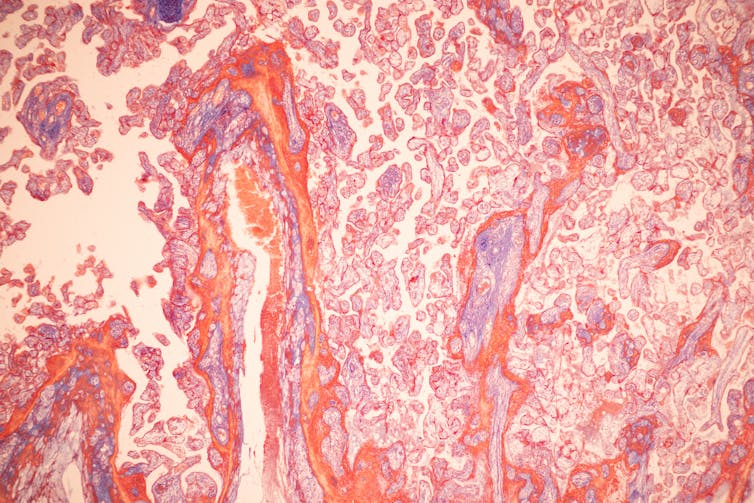

Sinhyu/iStock via Getty Images Plus

Kolliopoulos et al./Frontiers in Bioengineering and Biotechnology, CC BY-SA